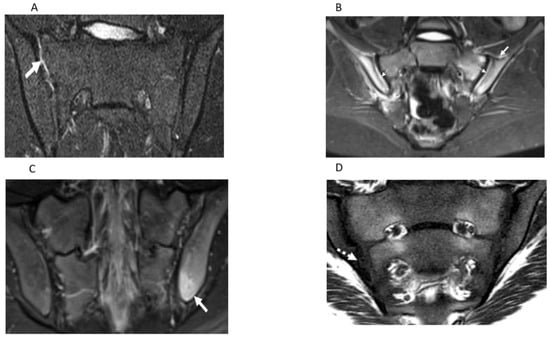

| Features | Definitions | Scores |

|---|---|---|

| Inflammation MRI Components | Score range/slide | |

| BME | An ill-defined area of high bone marrow signal intensity † within the subchondral bone in the ilium or sacrum on fluid-sensitive images | Score 4 quadrant/SIJ 0/1, range 0–8 |

| BME Intensity | Hyperintensity of the marrow edema using the presacral veins as reference | Score each SIJ 0/1, 0–2 |

| BME Depth | Continues to increase the signal of depth ≥ 5 mm/ ≥ 1 cm from the articular surface | Score each SIJ 0/1, 0–2 |

| Capsulitis | High signal on fluid-sensitive and/or post-contrast enhancement involving the SIJ capsule | Score halves / SIJ 0/1, 0–4 |

| JSI | Increased signal on fluid-sensitive or contrast-enhanced T1-weighted images within the joint space of the cartilaginous portion of the SIJ | Score halves/ SIJ 0/1, 0–4 |

| Enthesitis | High signal in bone marrow and/or soft tissue on a fluid-sensitive sequences or a contrast-enhanced T1-weighted sequence at sites where ligaments and tendons attach to a bone | Score each case 0/1, 0–1 |

| Structural MRI Components | ||

| Sclerosis | A substantially wider than normal area of low subarticular bone signal on T1-weighted and fluid-sensitive images (of ≥5 mm in adolescents) | Score 4 quadrants/SIJ 0/1, 0–8 |

| Erosion | Bony defect (or irregularity with associated bone marrow edema, sclerosis, or fatty lesion) at the osteochondral interface involving both contour and signal on both T1-weighted and fluid-sensitive images | Score 4 quadrants/SIJ 0/1, 0–8 |

| Fat Lesion | Increased homogenous signal intensity on T1-weighted non-FS image in subchondral bone with a distinct border | Score 4 quadrants /SIJ 0/1, 0–8 |

| Backfill | A bright signal on a T1-weighted sequence in a typical location for an erosion, with signal intensity greater than normal bone marrow, and meeting the following requirements. 1. It is associated with complete loss of the dark appearance of the subchondral cortex at its expected location. 2. It is clearly demarcated from adjacent bone marrow by an irregular band dark signal reflecting sclerosis at the border of the original erosion | Score halves/SIJ 0/1, 0–4 |

| Ankylosis | Presence of signal equivalent to regional bone marrow continuously bridging a portion of the joint space between the iliac and sacral bones | Score halves/0/1, 0–4 |